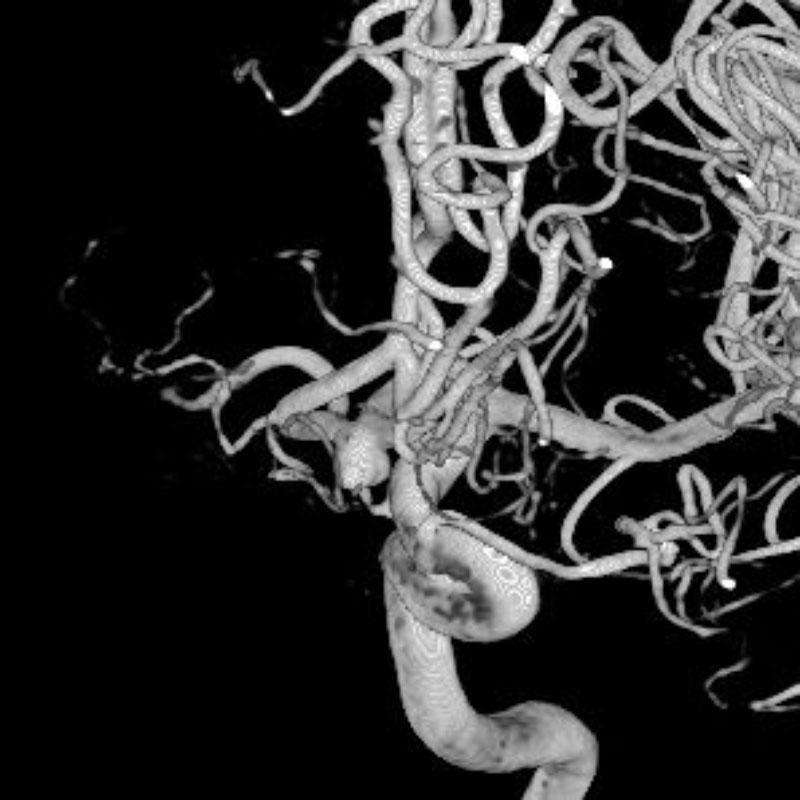

脳血管内手術症例

画像

5月20日(水)

左頚部内頚動脈狭窄症

経皮的頸動脈ステント留置術

須山/松田/濵田